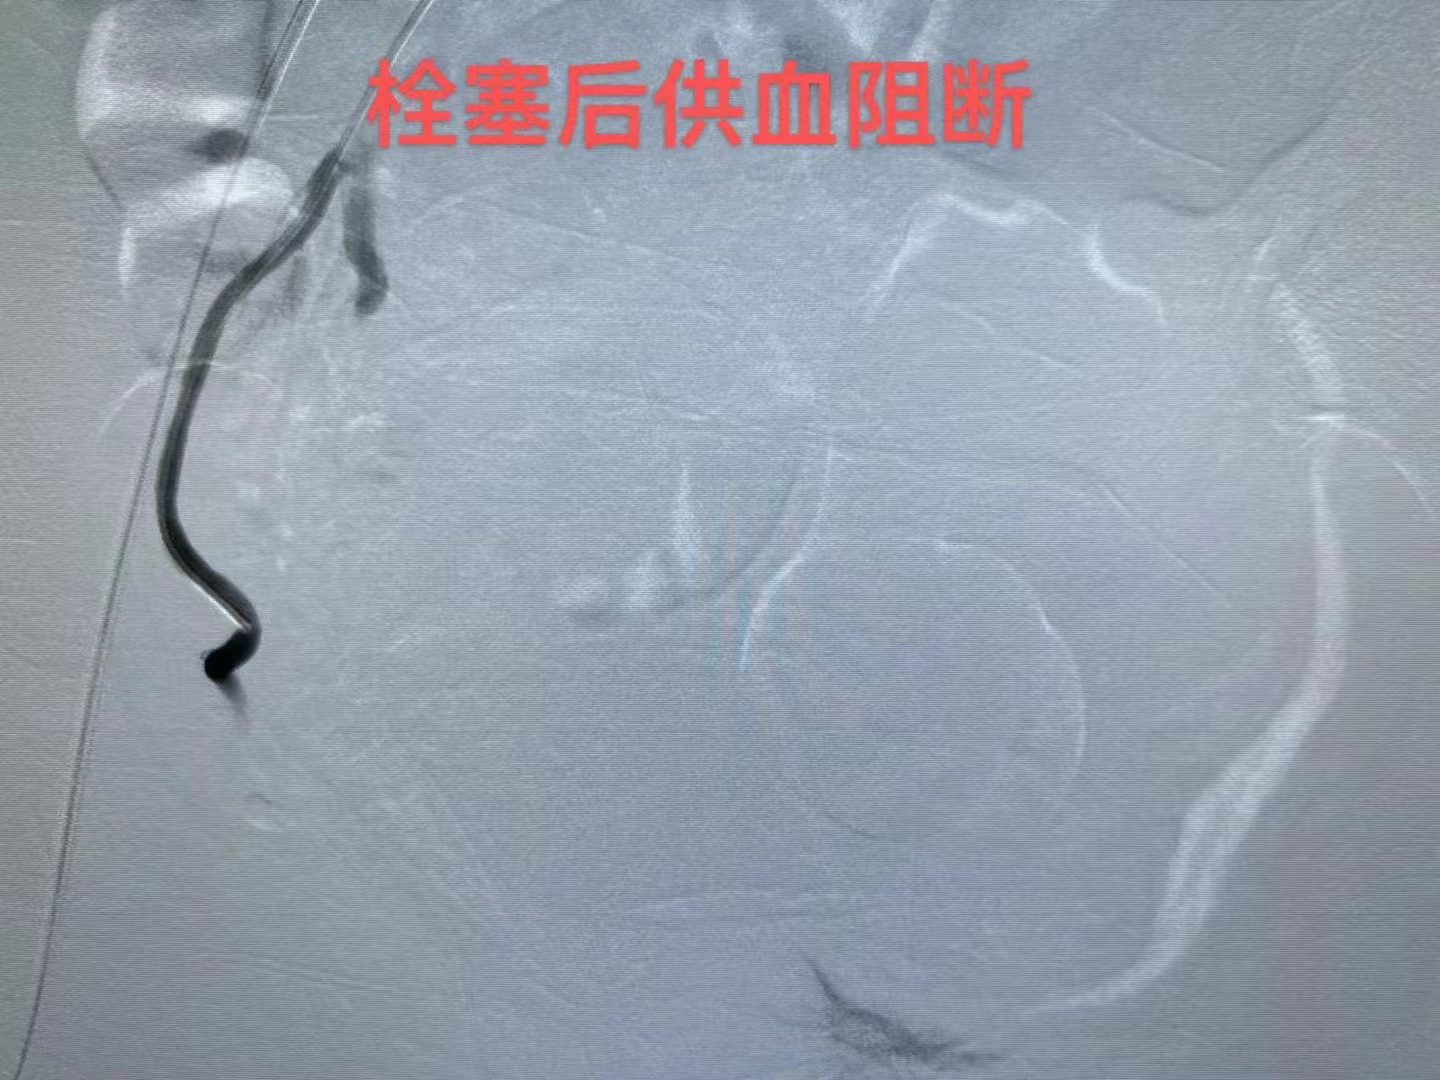

具体来说,这种治疗方法是通过子宫动脉造影,经右股动脉刺入导管,直接注入栓塞微球堵塞异位子宫内膜的供血血管,直接切断子宫腺肌症异位的子宫内膜血液供应,使腺肌症病灶被“活活饿死”。

子宫动脉栓塞术是目前保留子宫、治疗子宫腺肌症的有效手段之一,能很好地保留腺肌病子宫器官和功能的完整性。